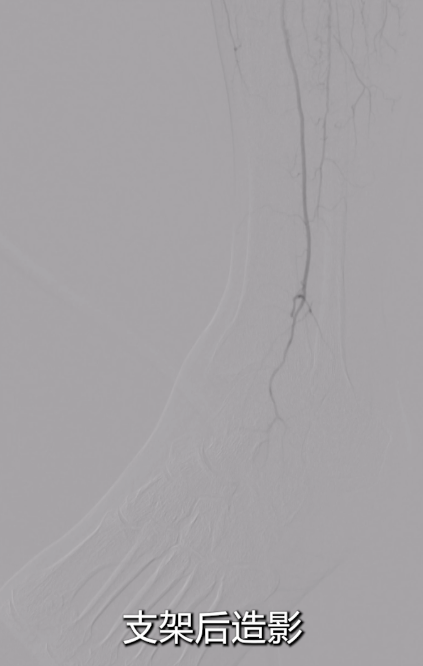

术后效果

即时造影:支架贴壁良好,病变段完全覆盖,膝下腓动脉及胫后动脉显影明显改善,胫后动脉血流可至足趾;

术后ABI:左侧ABI从术前0.32升至0.67,右侧1.09;患者症状改善,左足皮肤发紫发黑明显缓解,静息痛消失。

术后1月复查CTA,血管通畅性良好。给予双通道抗凝+抗血小板治疗,预防血栓再形成。